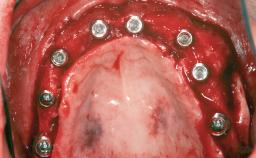

A 46-year-old woman was referred for treatment whose main complaints were mobility of her fixed partial dentures (right maxilla and left mandible) and periodontal bleeding during function. She also reported having taken systemic antibiotics to treat recurrent swelling in the area of the upper left molars. The patient had not seen a dentist for at least 2 years. She did not smoke and had no history of major systemic disease other than two minor orthopedic procedures some years back. The first-visit examination revealed poor plaque control, tooth mobility, periodontal disease, and a residual dentition widely associated with deep periodontal pockets.

| # of Teeth | 5 |

| # of Implants | 3 |

| Bone Augmentation | Horizontal|Staged|Vertical |